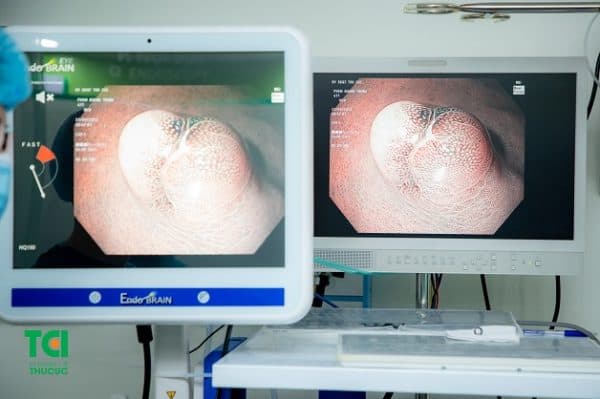

Nội soi phát hiện polyp đường tiêu hóa tại Hệ thống y tế Thu Cúc TCI